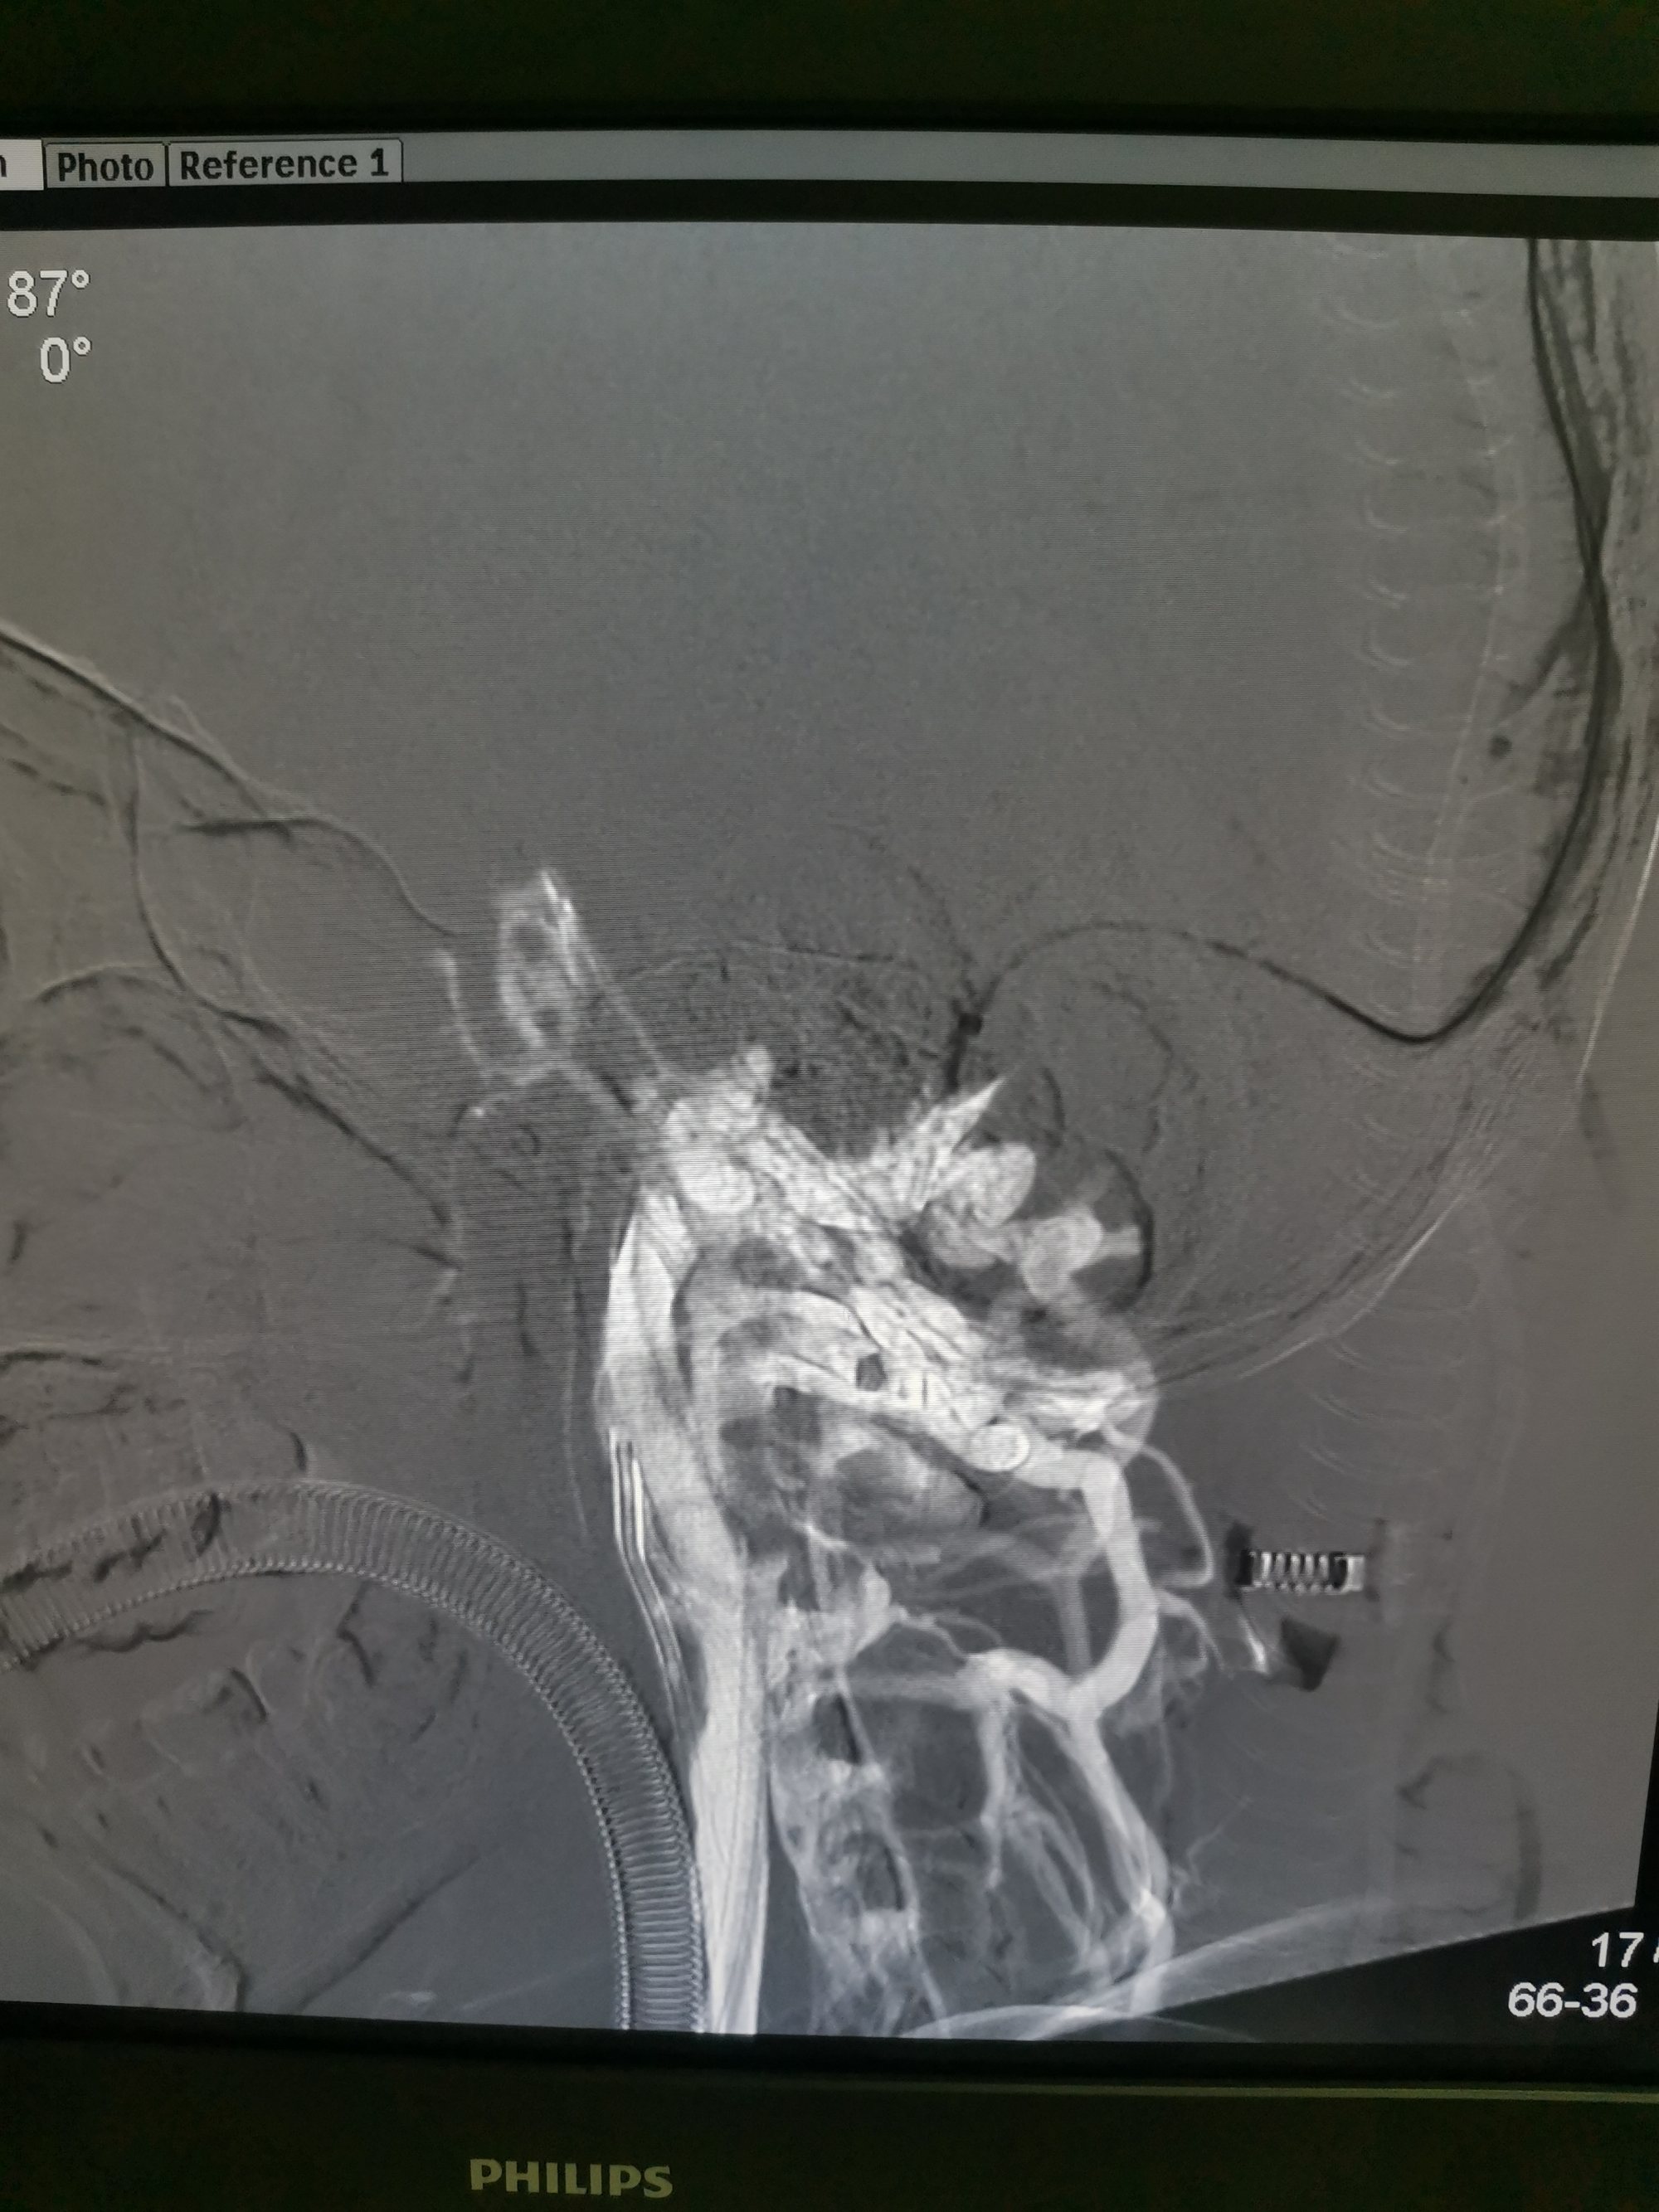

微导管微导丝经颈静脉入路将中间抽吸导管带入矢状窦。

抽吸导管上行过程中在横窦部位上行困难,抽吸无法抽出血栓。微导管在微导丝引导下到达矢状窦起始部位微导管造影见矢状窦起始部位血栓影,血流无法经矢状窦回流,经额极静脉逆向经颅底向颅外段静脉引流。

在矢状窦起始部释放取栓支架锚定后将中间导管带入支架近端。

中间导管到位后冒烟确定血栓位置。

Swim技术取栓以后矢状窦起始部血流通畅

支架取出部分血栓,抽吸导管抽出大量血栓

后移中间导管,抽吸与支架相结合继续取栓。

取栓过程

取栓过程

取栓后矢状窦血流恢复通畅。

最后关头动脉短鞘竟意外从股动脉内脱出,无法行动脉造影,遗憾!只能行静脉手推造影,矢状窦恢复正向血流。

矢状窦仍有部分血栓,局部有狭窄,术后给予抗凝抗血小板治疗。术后患者意识清醒,肢体运动同术前,语言功能正常。